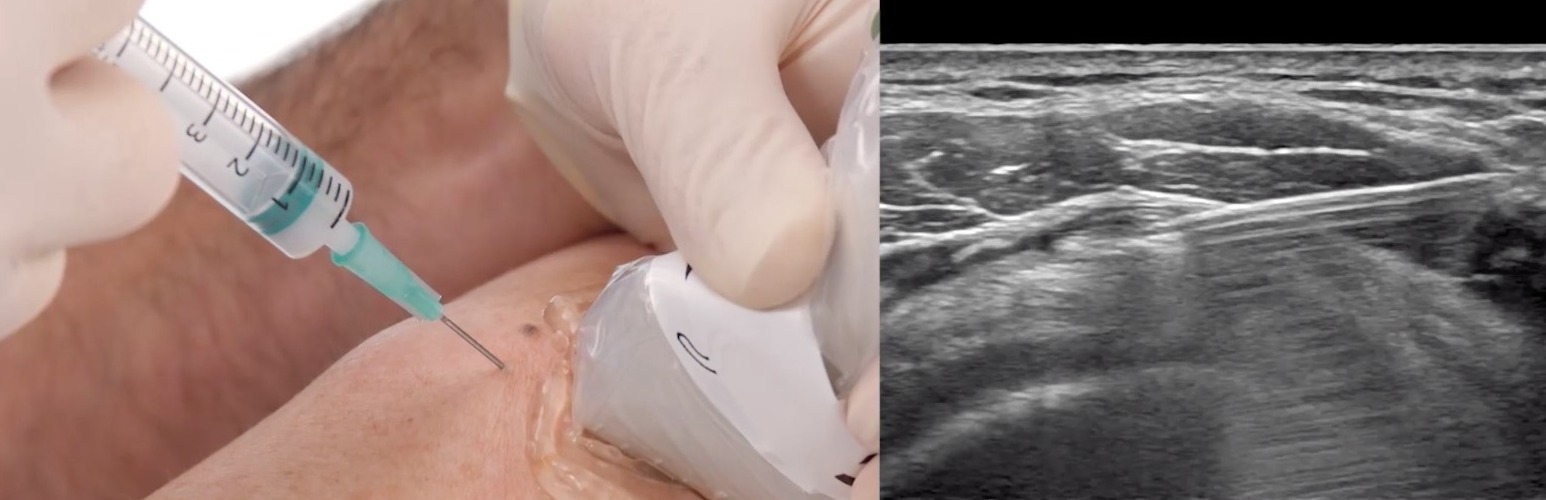

Consulta WALK-IN - Alívio imediato da DOR

Evite idas às Urgências. Connosco na Consulta WALK-IN, pode obter uma ajuda rápida e eficaz no alívio da sua dor